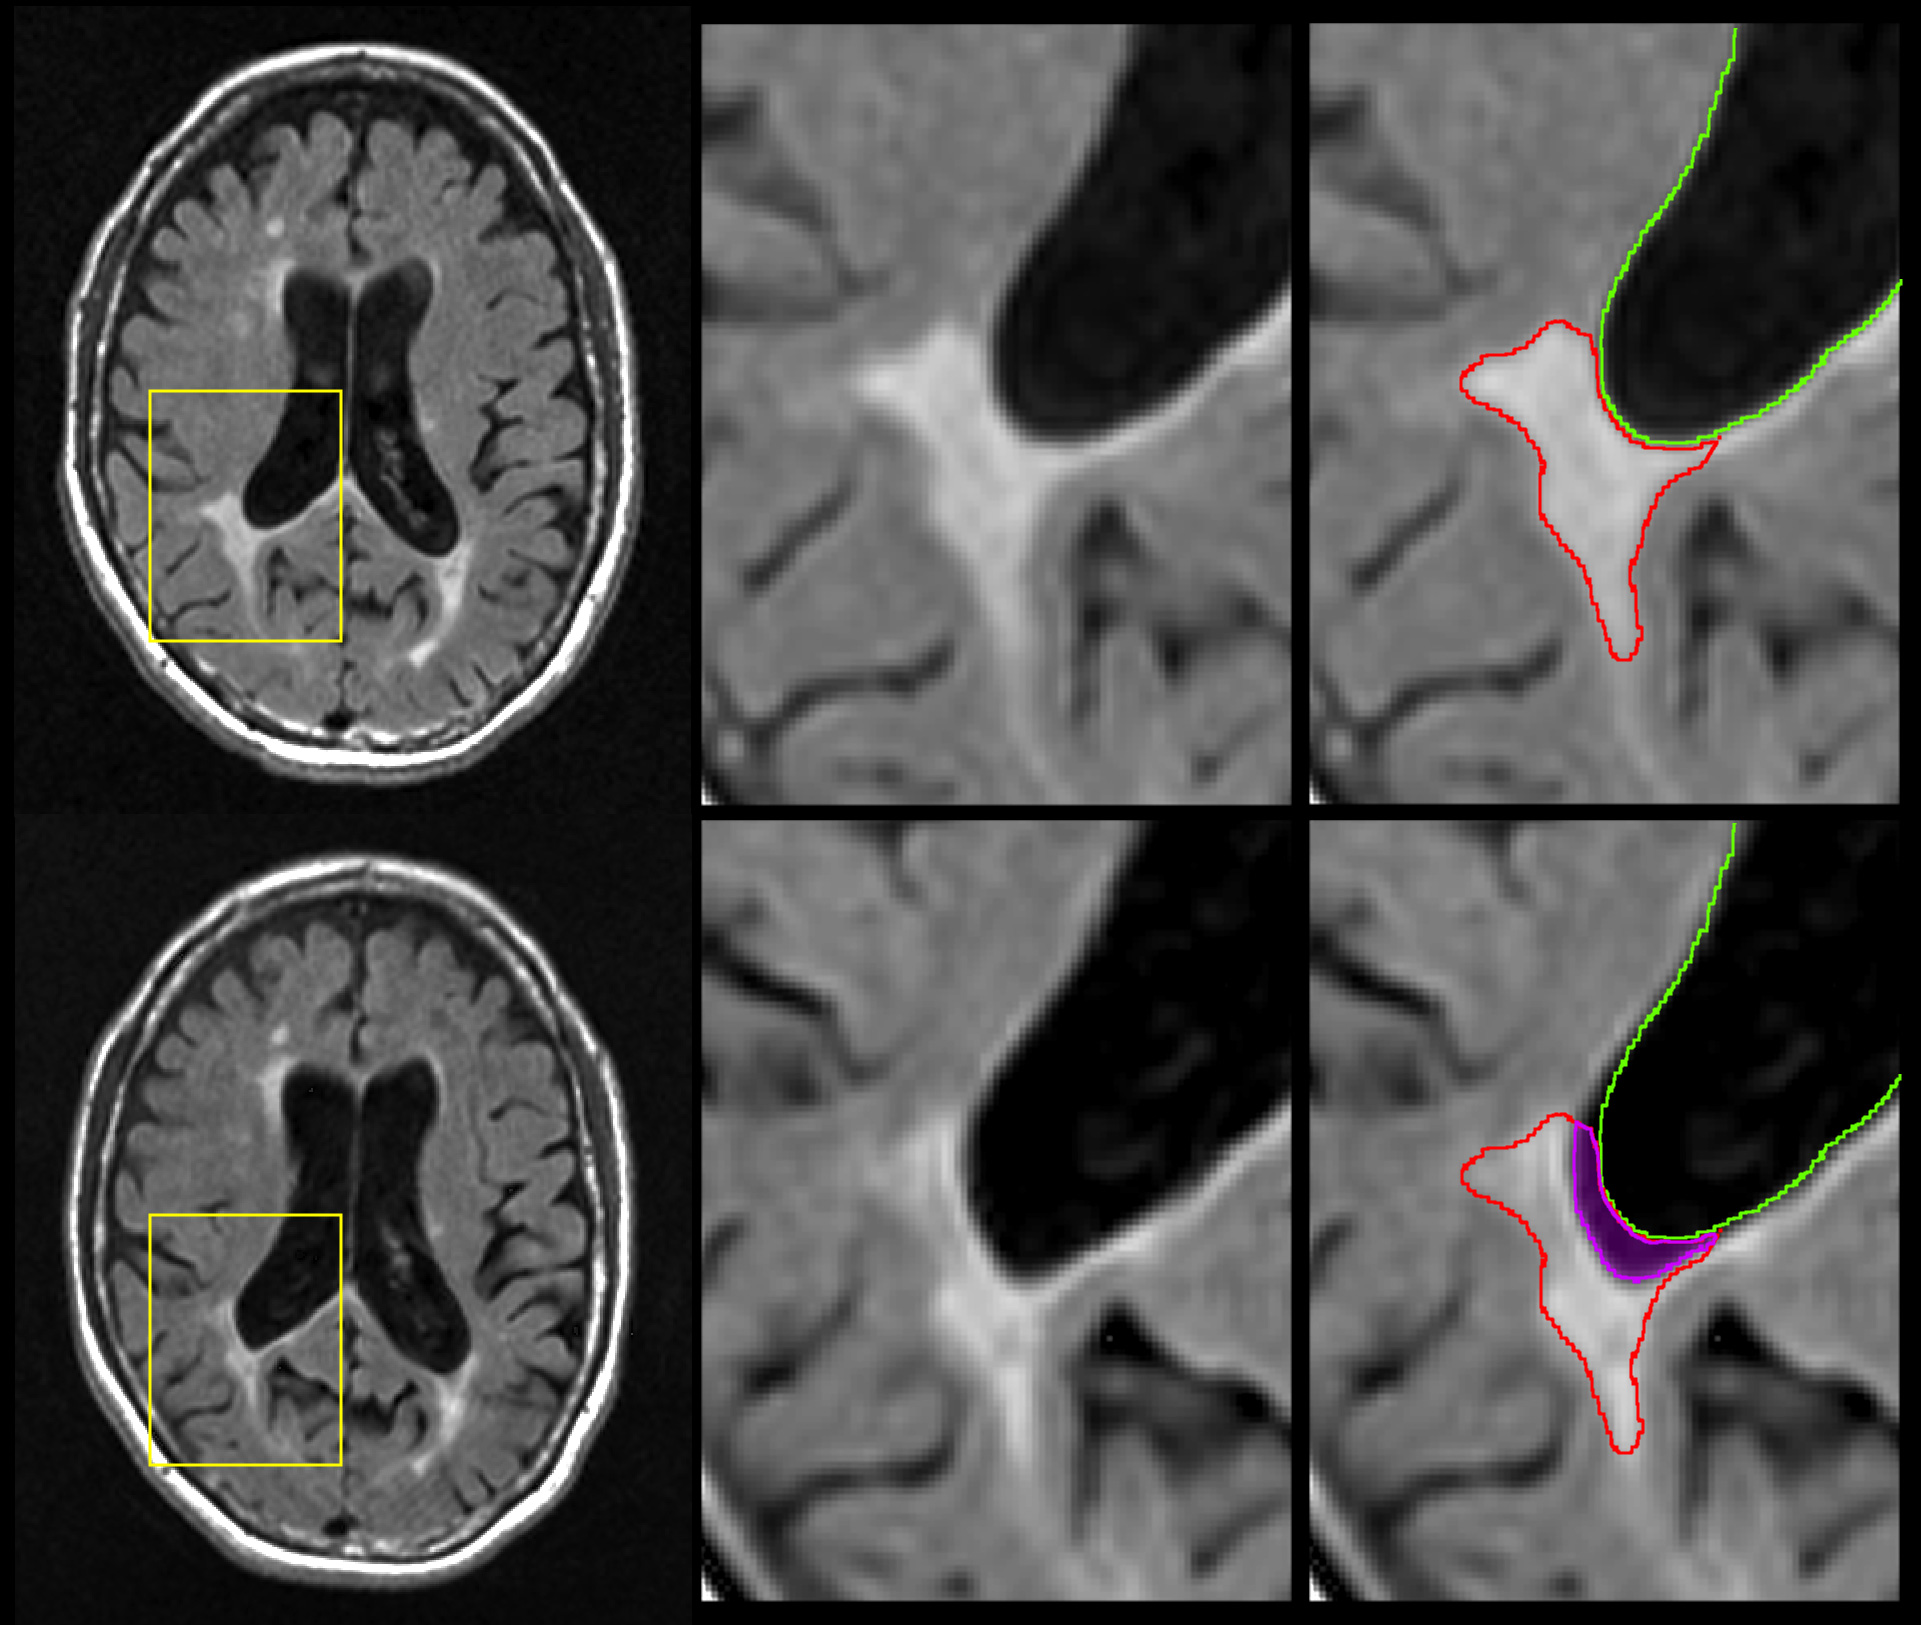

Representative example of an atrophied ("disintegrating") lesion. Top row shows baseline MRI images, and bottom row shows follow-up MRI images. The magenta region in the bottom right panel shows the part of the original lesion (top) that has disintegrated into cerebrospinal fluid over the intervening period. Nearly 20% of the lesion was lost over time. (Image: Michael G. Dwyer)

In order to focus specifically on the disappearance of lesions that likely indicate pathological change like atrophy, not beneficial change, like resolution or remyelination, the researchers looked exclusively at lesions seen on previous scans that were later replaced by cerebrospinal fluid.

“How do we know the lesions have disappeared?” asked Zivadinov. “Because where there was brain lesion tissue before, there now is just fluid.”

The researchers looked specifically at the rate of brain lesion loss due to atrophy compared to accumulation of lesion volume seen both at baseline and follow-up. They found that the amount of lesion volume that atrophied was the only significant lesion parameter that correlated with clinical disability as measured by the Expanded Disability Status Scale (EDSS), the most widely used method of quantifying disability in MS.

“Paradoxically, we see that lesion volume goes up in the initial phases of the disease and then plateaus in the later stages,” said Zivadinov. “When the lesions decrease over time, it’s not because the patient lesions are healing but because many of these lesions are disappearing, turning into cerebrospinal fluid.”